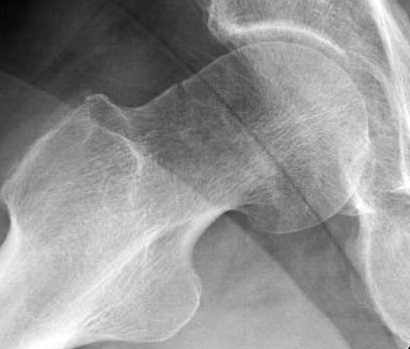

Уважаемые коллеги,

Хотели бы знать тактику лечения 62 летнего больного, отягощенного

алкоголизмом, с жалобами на боли в правом тазобедренном суставе.

Не смогли добиться вразумительного ответа по поводу анамнеза травмы,

клинически движения ограничены из-за боли, сделанные снимки сустава

представлены. На КТ неполный перелом шейки. Начали профилактику

возможного Алкогольного Делирия.

Дальнейшее рекомендации, оставить как есть, или профилактическая

перкутанная фиксация?